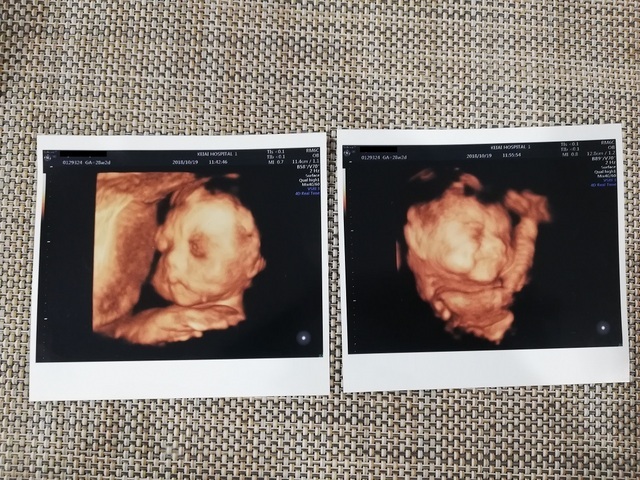

28週2日(28w2d・女の子)|わっつ さん(38歳)

エコー写真撮影時のエピソード:

このエコーの二週間前から逆子で、このエコーの時も逆子でした。体調もよく、上の子も産まれてくるの楽しみに待ってます。

写真が男の子っぽい顔だったので、男の子かなと思ってまた、次の検診で聞いてみたんですが、女の子でした。長男はちょっとがっかりな感じでしたが、どちらでもうれしいみたいです。